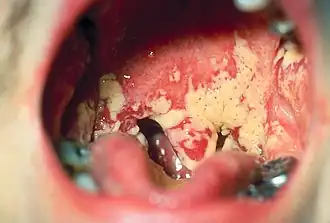

Orale candidiasis

Spruw, klachten door Candida albicans in de mond. C. Albicans kan bij veel mensen in het speeksel worden aangetoond, zonder dat het mondslijmvlies aangetast is. In dit geval is er dan ook geen sprake van candidose. Het percentage van mensen waarbij Candida albicans in de mond kan worden aangetoond is 40%.[1] Risicofactoren zijn een (slecht passend) kunstgebit, antibioticagebruik, roken en diabetes. Een andere oorzaak van orale candidiasis is echter het gebruik van hoge doses inhalatiecorticosteroïden, die deels in de mondholte neerslaan en ter plaatse de weerstand van het slijmvlies onderdrukken. Om deze reden wordt bij hoge doseringen van deze inhalatiegeneesmiddelen aanbevolen na het inhaleren de mond te spoelen.[2]

Orale spruw bij volwassen is ongebruikelijk en kan het gevolg zijn van hiv of aids of chemotherapie. Ook malnutritie speelt een rol: het kan een gevolg zijn van een tekort aan vitamine B12 en ijzer.[3]